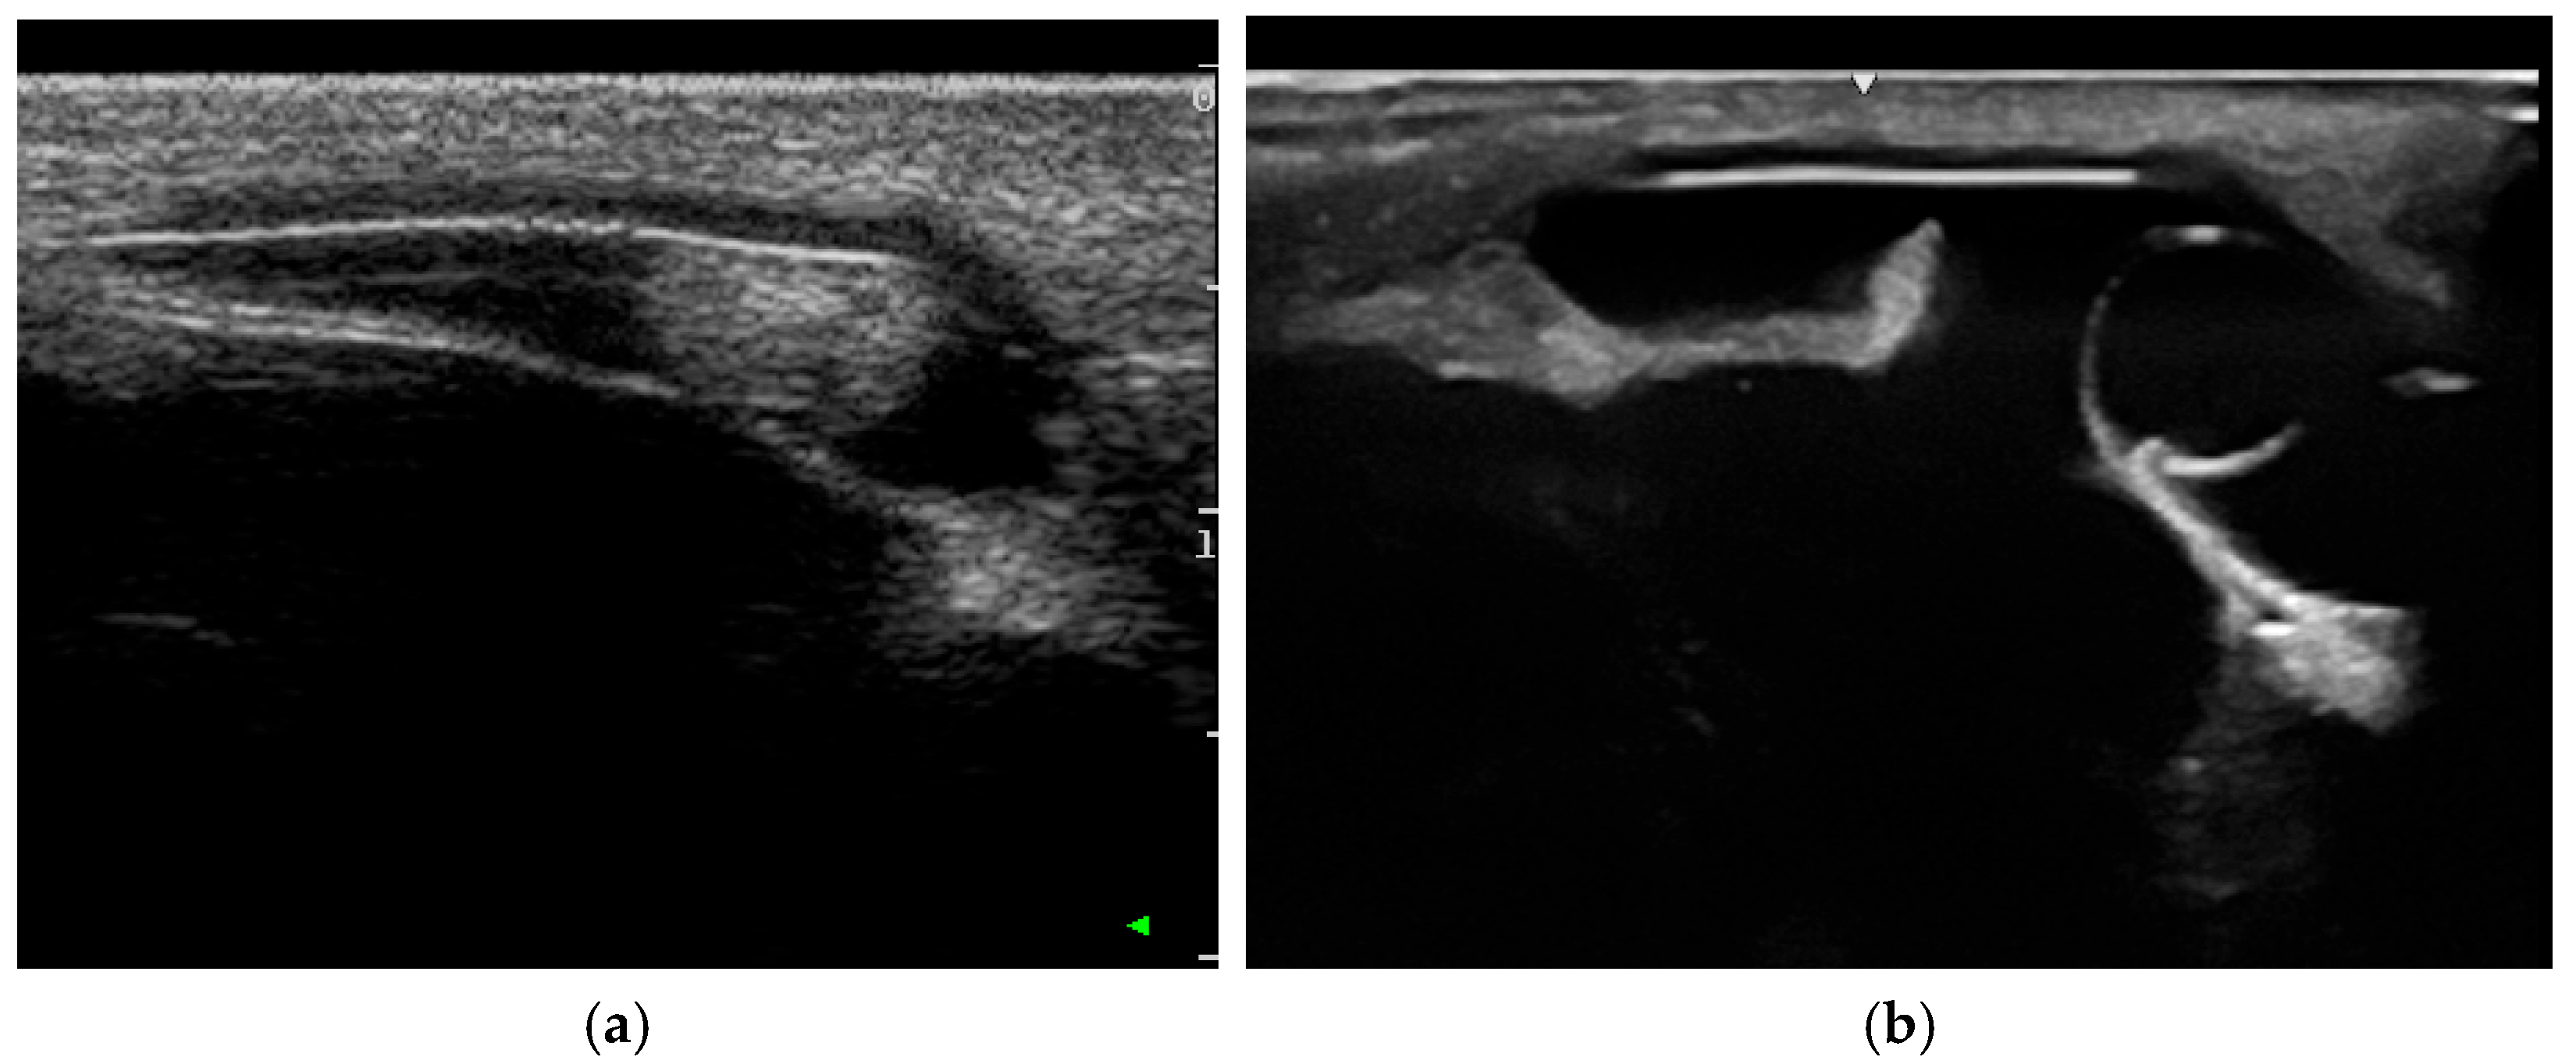

3.2.1. Ultrasonography

3.2.2. Sectional Imaging